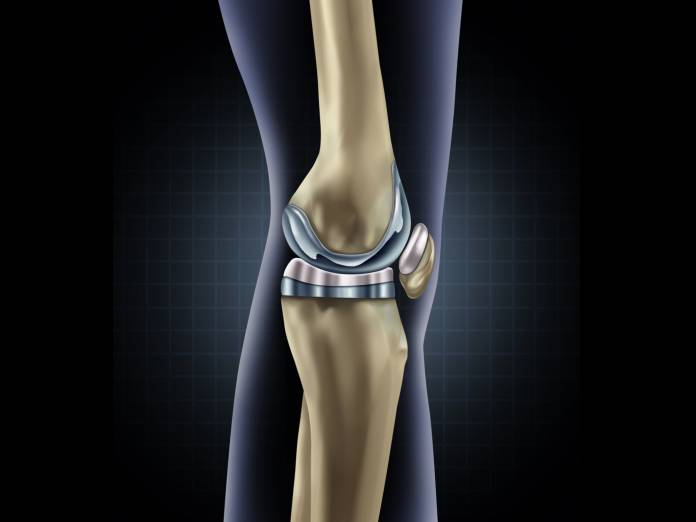

Zum Gelenkersatz gibt es mehrere Prothesenarten von verschiedenen Herstellern. Welche Möglichkeit gewählt wird, hängt von den individuellen Umständen ab, so unter anderem vom Zustand der Gelenkkapsel und der Bänder sowie vom Allgemeinzustand des Patienten. Meist wird eine Total-Endoprothese eingesetzt, bei der die gesamte Verbindung von Oberschenkelknochen und Schienbein erneuert wird (Knie-TEP). Nur manchmal genügt eine Teilprothese.

Die einfachste Art der Total-Endoprothese ist die Oberflächenprothese. Dabei werden die angegriffenen Gelenkflächen aus Knorpel vom Oberschenkelknochen und Schienbein zusammen mit einer dünnen darunterliegenden Knochenschicht abgetragen. Die freiliegenden Knochenflächen werden so bearbeitet, dass sich die Prothese genau einfügt. Diese wird dann an den beiden Knochen befestigt.